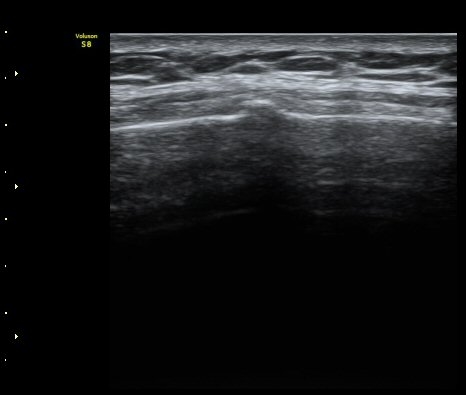

¹Ì¼¼ÇÏ°Ô °¥ºñ»À ÇÇÁú°ñ ¿¬°á¼º ¼Ò½ÇÀÌ °üÂûµÊ(loss of cortical continuity of rib)  »çÁø 1, 2

°¥ºñ»À ¹Ì¼¼°ñÀýÀÌ È®ÀÎ µÊ